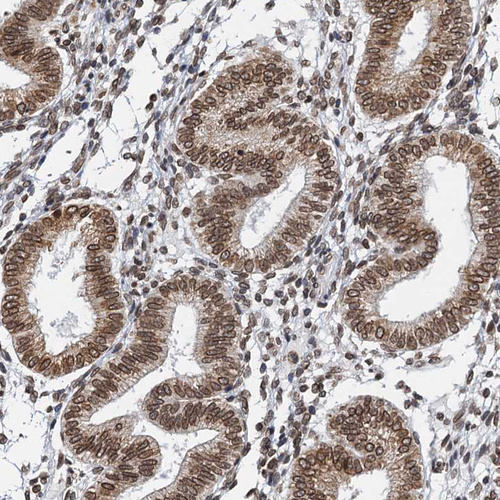

Immunohistochemical staining of human endometrium shows strong nuclear positivity in glandular cells.